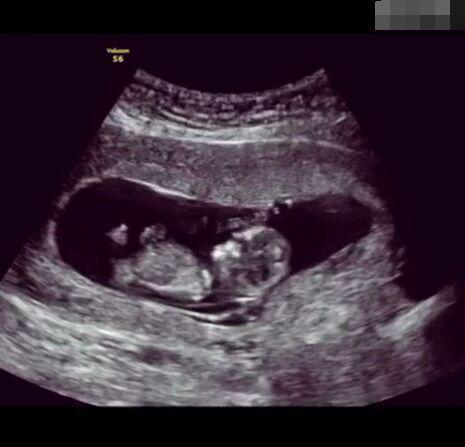

懷孕后,寶寶的性別一直是全家人的重點(diǎn)關(guān)注對(duì)象。而男女性別的差異,在基因?qū)用骟w現(xiàn)在第二十三對(duì)染色體上,如果是XY則是男孩,XX則是女孩,這都是由那枚與卵子結(jié)合的精子來(lái)決定。

那些做了B超檢查確定胎兒男女,生下來(lái)后發(fā)現(xiàn)不對(duì)的,多半是因?yàn)樵贐超檢查時(shí)寶寶太調(diào)皮,以致影響了檢查準(zhǔn)確性。就比如說(shuō),有的女寶寶在媽媽肚子里玩自己的臍帶,把臍帶夾到了兩腿中間,B超就有一定幾率拍出來(lái)好像是男寶寶的特征,導(dǎo)致被誤認(rèn)為是男孩子。還有些男寶寶過(guò)分害羞,在做B超時(shí)雙腿緊緊并攏,醫(yī)生也很難判斷男女,只好大致猜測(cè)是女孩,就又造成了誤會(huì)。因此,B超亦不是萬(wàn)能的。